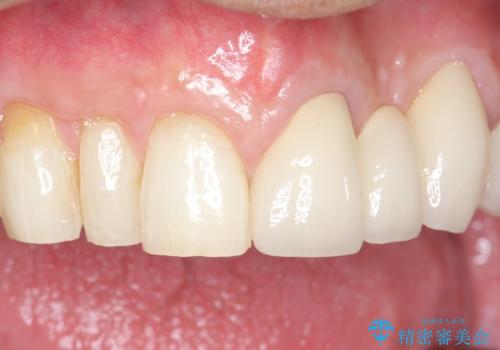

牽引により歯の保存が可能となり、ブリッジによる補綴を行うことができました。

健全歯質を歯肉縁上に出すためにしっかり挺出させたことで歯根長が短くなりましたが、仮歯で十分に保定した結果動揺度Ⅰ程度となり、ブリッジの支台歯にすることが可能と判断しました。

患者様には「抜歯適応の歯を残せて嬉しいし、とても丁寧に治療して頂けた」と大変喜んで頂けました。

クラウンの種類:オールセラミッククラウン スタンダード